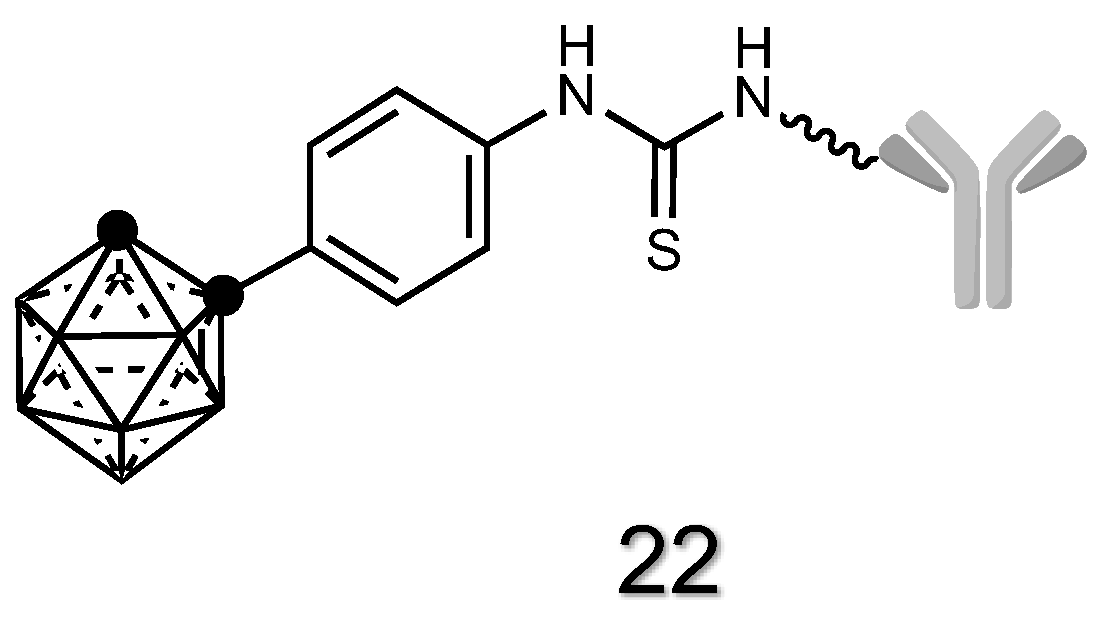

2.1.8. Antibody Derivatives of Carboranes